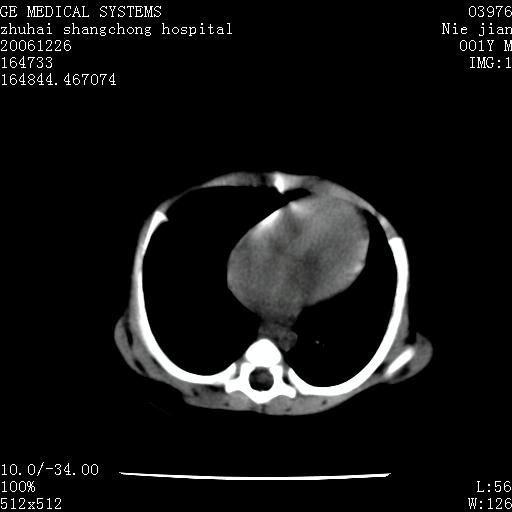

3个月婴儿腹胀来看。

【影像特征】

1、肝明显增大,肝弥漫性低密度灶。

2、肾上腺区见类圆形肿块,其内密度不均,见片状偏高密度。

1、肝弥漫性病变,考虑急性肝炎致广泛脂肪浸润可能性大。

2、肾上腺区占位,假性肿瘤?肾上腺血肿(感染所致)?

1、关键着眼点:肝脏弥漫性病变内有没有走形的血管,仔细看部分低密度内有血管影(要有增强扫描作为证据就好了),说明并非肿瘤样病变,而是脂肪浸润。即可能不是转移瘤或原发肿瘤,低密度的形态上看,是片状,也不像肿瘤。

2、儿童肝炎最常见的是感染,有时食入性损害或药物也可致肝脏炎症,肝炎致大空泡型脂肪变性,是一种无痛性疾病,无症状,病因有营养异常、代谢性疾病、药物及病毒感染。所以脂肪变性与感染有关。